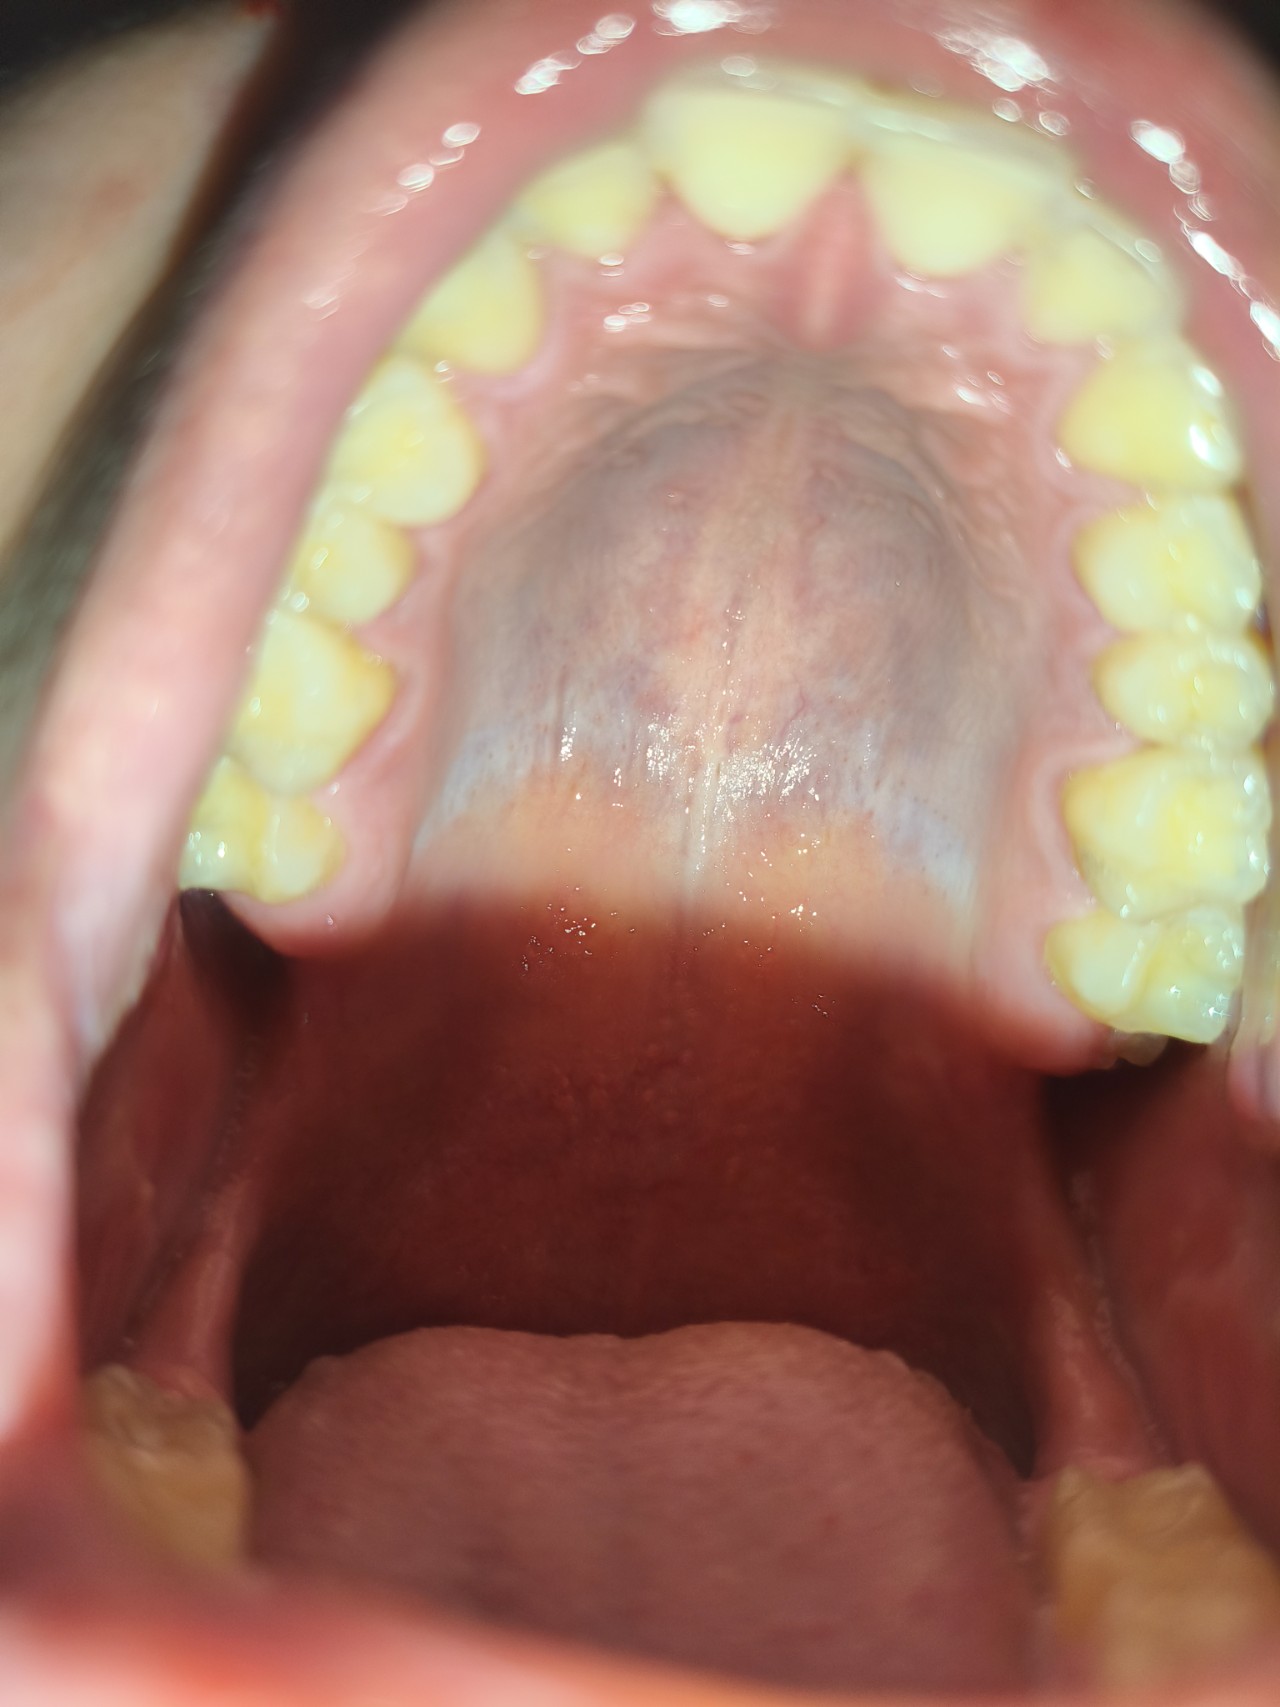

Здравствуйте, недавно заметил, что мое нёбо, ближе к зубам, серого цвета. Никакого дискомфорта не испытываю, это не налет. Подскажите, пожалуйста, чем это может быть вызвано.